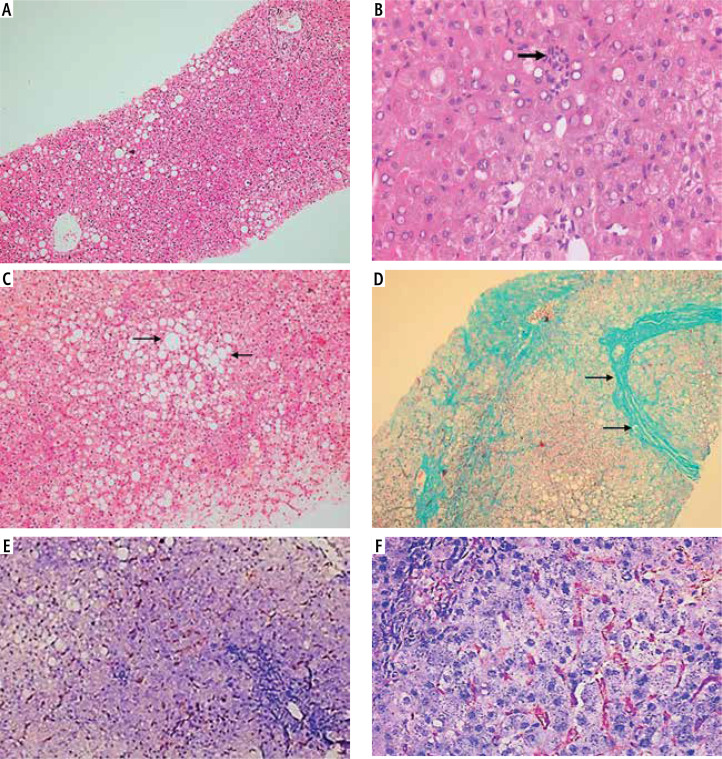

Aim of the study: Metabolic associated steatotic liver disease (MASLD) is one of the most frequent chronic liver diseases in the world; macrophage activation is reflected by increased expression of CD163, which sheds as serum soluble CD163 that is linked to hepatic steatosis, inflammation, and fibrosis. Aim of the study was assessment of liver macrophage activation and hepatic histopathological changes in patients with MASLD.

Material and methods: A total of 30 patients with MASLD and equal numbers of age- and sex-matched healthy controls were enrolled in the study. Quantitative serum levels of soluble CD163 (sCD163) were determined using a commercially available standard sandwich ELISA kit. Core liver biopsies were obtained from patients with MASLD and evaluation of CD163 using anti-CD163 Ab-1 (Clone 10D6) - mouse monoclonal antibody.

Results: The median sCD163 level was significantly higher in patients with MASLD compared with healthy controls. It can discriminate patients with MASLD from healthy controls at a cut-off value of 814 pg/ml. sCD163 level and intrahepatic total CD163-positive cell count were positively correlated, and both showed positive correlations with nonalcoholic fatty liver disease activity score.

Conclusions: Soluble CD163 can discriminate MASLD patients from healthy controls after the exclusion of other causes of inflammation.